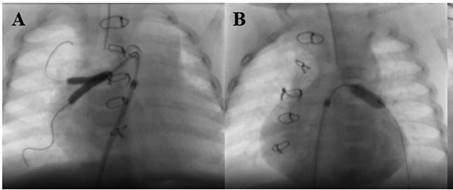

Se realizó una tomografía computarizada (TC) en la que se

observó trombosis de la vena yugular interna izquierda, con oclusión de las

venas braquiocefálica y subclavia izquierdas (Fig. 1).

Fig. 1. TC: plano axial. Desplazamiento de la carina por trombosis de la vena yugular y edema ipsilateral.